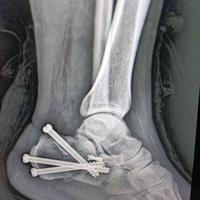

年轻男性患者,跟骨骨折微创螺钉固定。

年轻男性患者,跟骨骨折微创螺钉固定。...